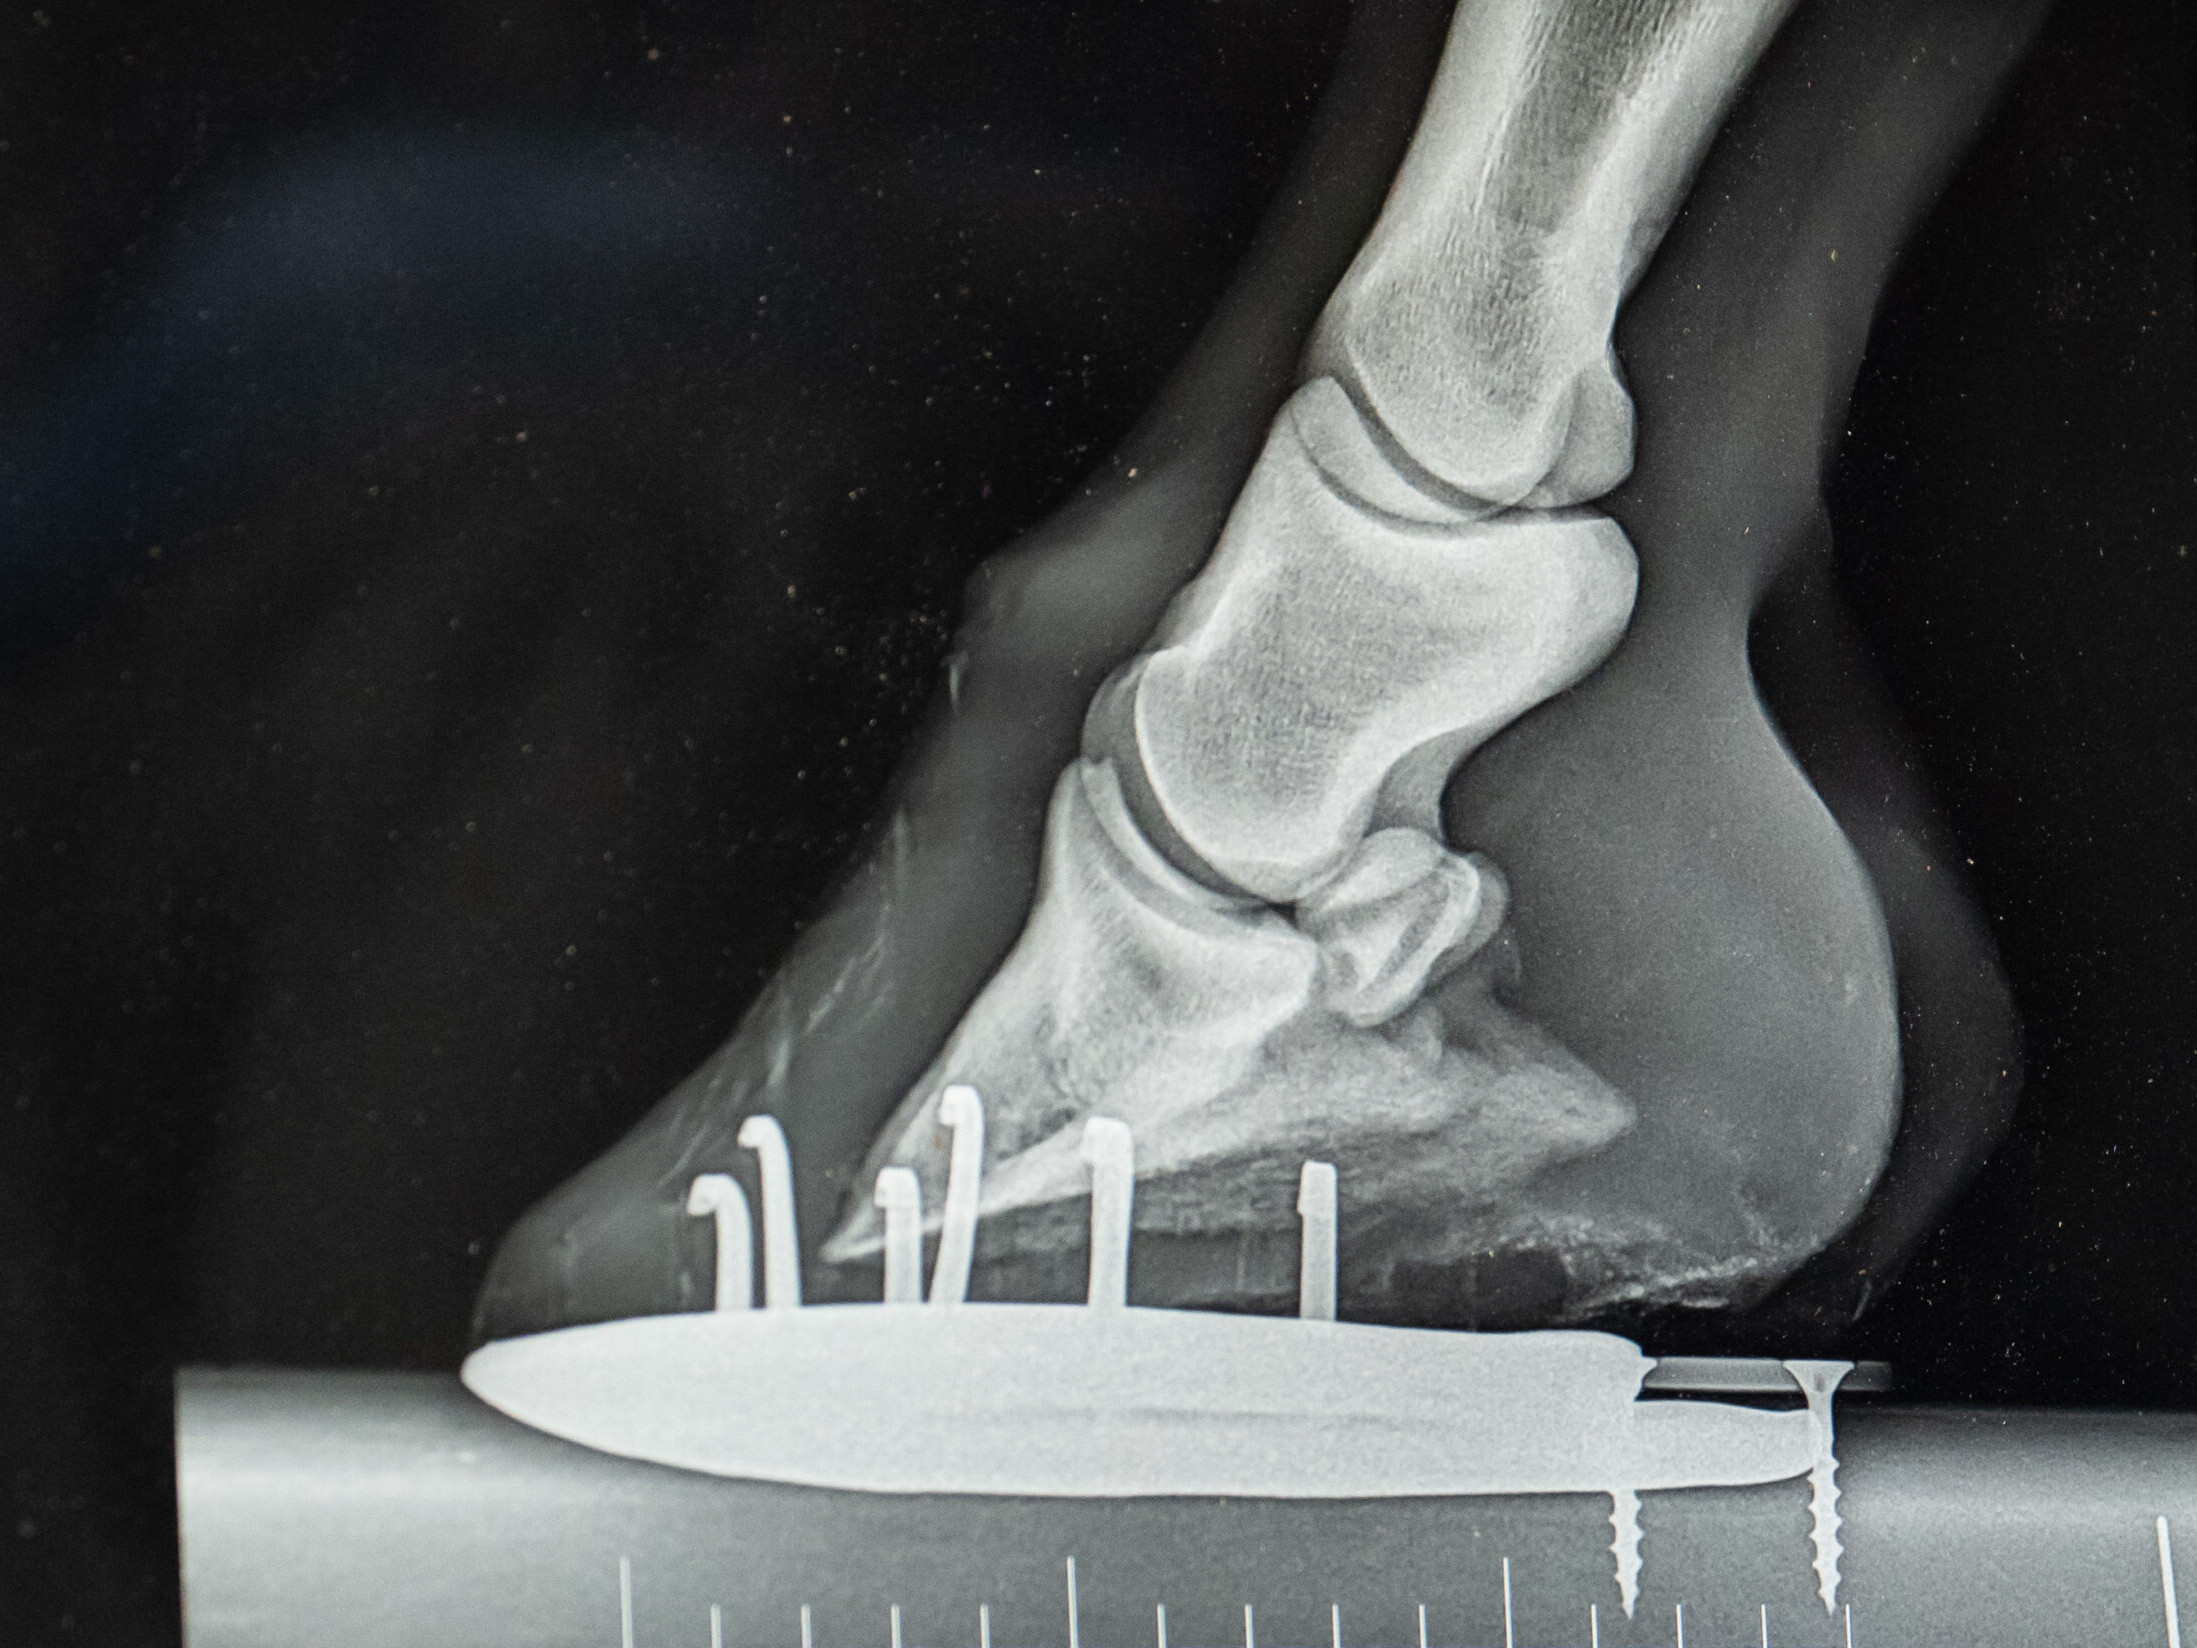

- Digitale röntgenologische Untersuchungen

Orthopädie

- Lahmheitsdiagnostik